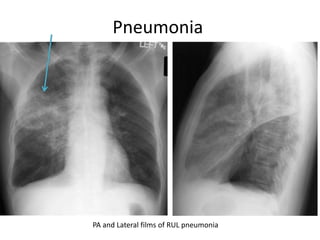

PA and Lateral films of RUL pneumonia

Right upper

lobe

pneumonia